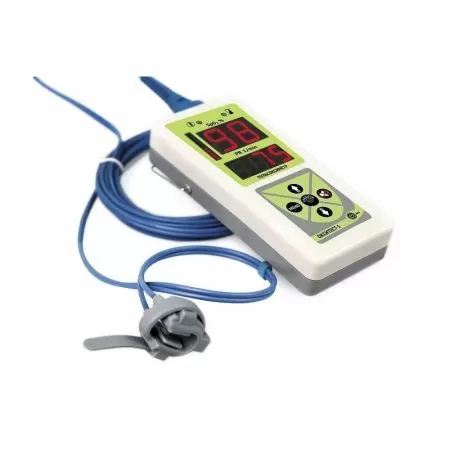

Датчик пульсоксиметрический пальцевой |

1 |